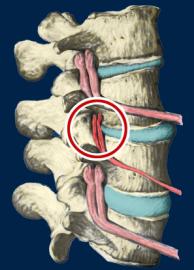

This is a representation of one type of subluxation. A subluxation, as defined by the Association of Chiropractic Colleges is: "A subluxation is a complex of functional and/or structural and/or pathological articular changes that compromise neural integrity and may influence organ system function and general health." When a subluxation occurs it causes nerve interference in some portion of the body affected by those nerves. The subluxation causes changes to the structure as well as the nerves. These changes get progressively worse as time is allowed to work on the subluxated area of the spine. These changes take the form of ongoing degeneration known as "subluxation degeneration". By understanding the type and amount of changes, it is possible to reasonably estimate the time subluxations have been present in a spine. Having this information is useful in understanding the time and effort needed for correction.